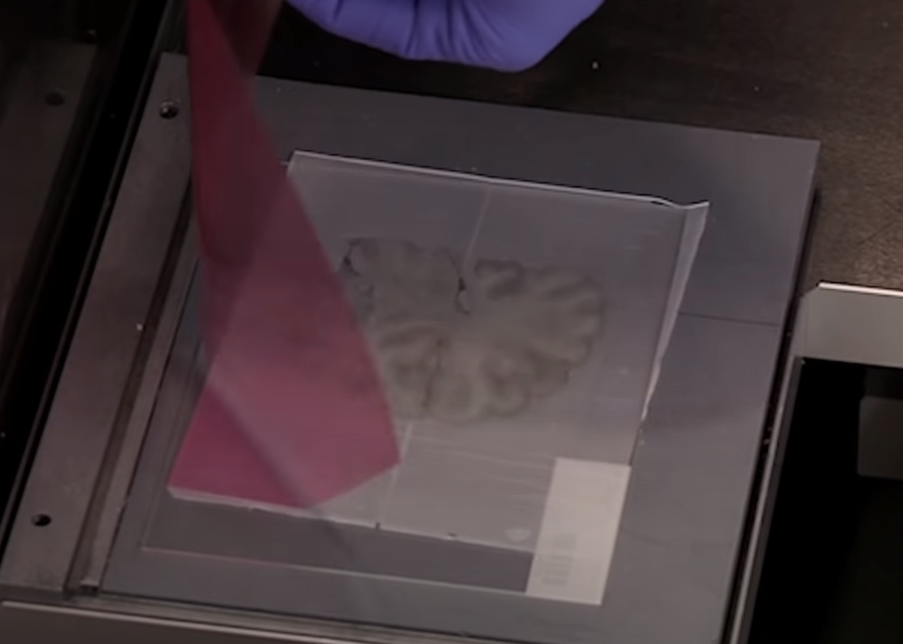

使它可以放在一个更小的低温恒温器上,切成20微米的厚度的薄片。

这里切下是冰冻的slice,让它融化在玻片上面。